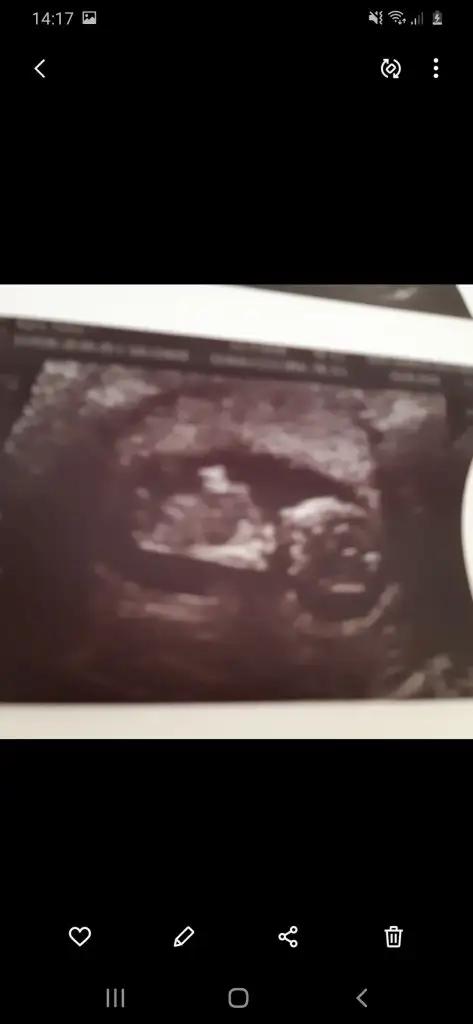

Ikra meyra Ikra meyra bize de bakabilir msn? Burda 12+5 olmasi gerekti ama 13+1 cikti. Onceki ultrasonlar yumurtalama gunume denk geliyordu sumde buyuk cikti anlamadim ki...

Eklentiler

• 94EA6533-4981-4F2A-A8D8-511BD20A867D.webp

94EA6533-4981-4F2A-A8D8-511BD20A867D.webp

44,1 KB · Görüntüleme: 105